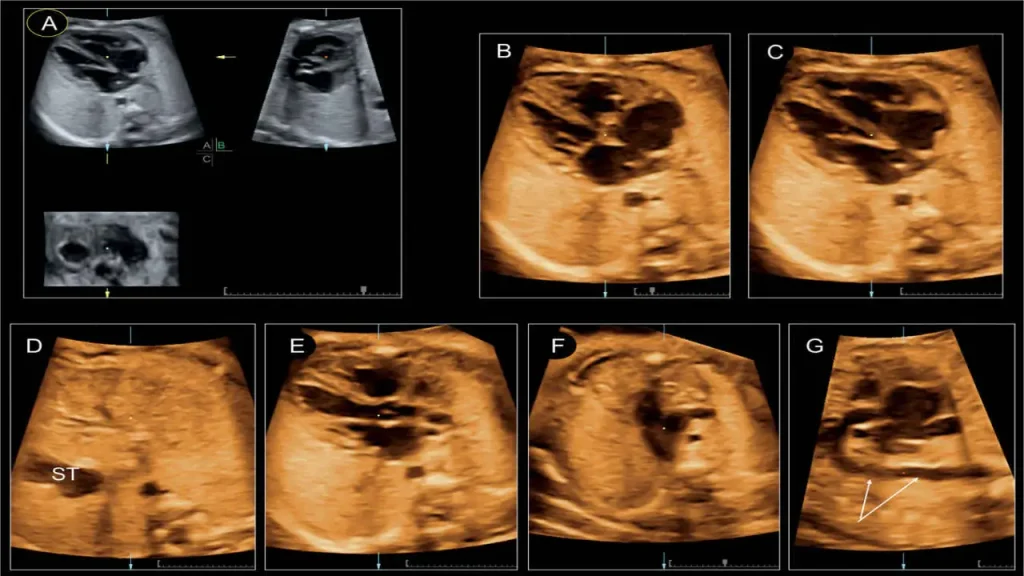

اکو قلب جنین یا Fetal Echocardiography نوعی سونوگرافی تخصصی است که به پزشکان امکان میدهد ساختار و عملکرد قلب جنین را در دوران بارداری با دقت بالا بررسی کنند. در این روش، دستگاههای پیشرفته با استفاده از امواج فراصوت تصویری دقیق از قلب، بطنها، دهلیزها، دریچهها، عروق اصلی و حتی ریتم قلب جنین ایجاد میکنند. به همین دلیل، اکو قلب جنین یکی از ابزارهای حیاتی برای تشخیص زودهنگام مشکلات قلبی محسوب میشود.

انتخاب زمان مناسب برای انجام اکو قلب جنین یکی از مهمترین عوامل در دقت و کیفیت نتایج است. متخصصان زنان و قلب کودکان توصیه میکنند که بهترین زمان برای انجام این بررسی بین ۱۸ تا ۲۲ هفته بارداری است. در این بازه، قلب جنین به اندازهای رشد کرده که بتوان ساختارهای اصلی آن مانند بطنها، دهلیزها، دریچهها و عروق اصلی را به وضوح مشاهده کرد. همزمانی این مرحله با سونوگرافی آنومالی هم باعث میشود پزشک یک ارزیابی جامع از سلامت جنین داشته باشد.

- کیفیت تجهیزات: دستگاههای پیشرفته با قابلیت Doppler و تصویربرداری سهبعدی دقت تشخیص را بسیار افزایش میدهند. به همین دلیل مراجعه به بهترین مراکز اکو قلب جنین اهمیت زیادی دارد.

ویستان از جدیدترین دستگاههای اکو با قابلیت Doppler و تصویربرداری سهبعدی و چهاربعدی استفاده میکند. این تجهیزات تصاویر شفاف و دقیق ارائه میدهند و امکان بررسی کامل ساختار قلب جنین را فراهم میکنند. - گزارشهای قابل فهم و جامع: